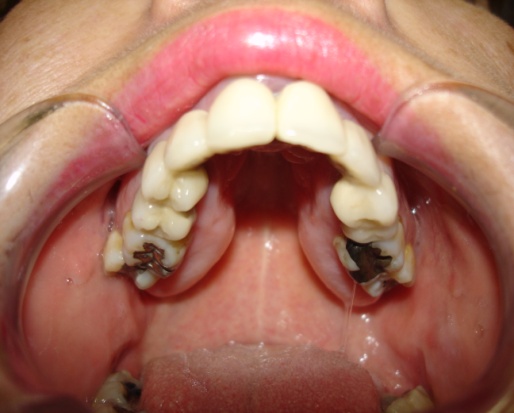

HIPOPLASIA MAXILAR Paciente operado de avance maxilar |

||